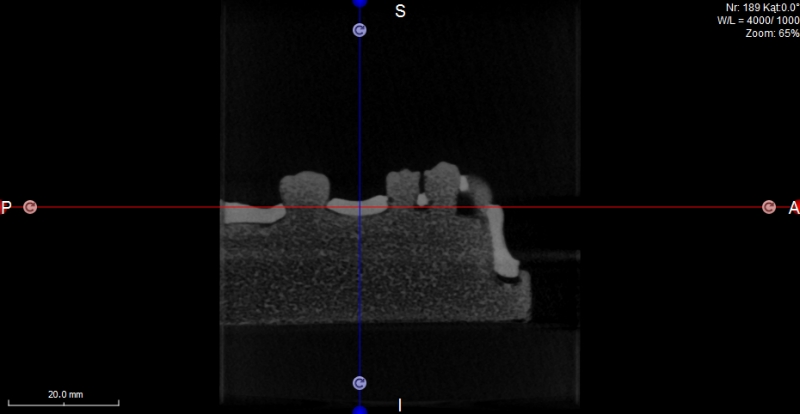

Oferujemy również szablony chirurgiczne przeznaczone do szkoleń z implantacji. Umożliwiają planowanie leczenia implantologicznego i przeprowadzenie szkoleń z wykorzystaniem plików CT, STL oraz druku 3D. Oferujemy nasze modele do szkoleń implantologicznych wraz z plikami DICOM i STL.

Model szczęki z zębami w pozycjach 11, 13, 14, 23, 24, 25 i 27, brakiem zębów w wygojonych pozycjach 21, 22, 26, 15, 16. Umieszczenie dwóch zagłębień imitujących niezagojone zębodoły w pozycjach 17 i 12 umożliwia ćwiczenie implantacji wczesnej i natychmiastowej. Wykonany jest z jednorodnego materiału o właściwościach zbliżonych do kości ludzkiej.  Model pokryty jest śluzówką, którą można nacinać i zszywać. Znakomicie nadający się także do  nauki implantacji odroczonej i planowania leczenia poekstrakcyjnego. Umożliwia również przedstawienie problemów związanych z prawidłowym umieszczeniem implantów pomiędzy koronami sąsiadujących zębów. Model można stosować w najbardziej popularnych na rynku fantomach jak i głowie fantomowej PROMEDICU 11-1000 jak również samodzielnie bez niego.